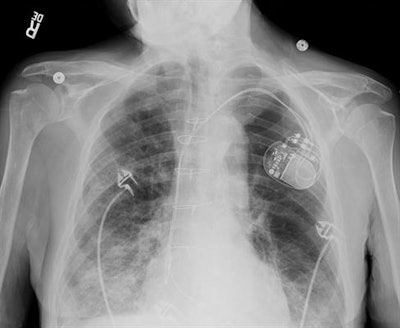

Samsung is looking to harness the growth of AI by discussing several products, including Bone Suppression, an algorithm that reduces signal from bone in chest x-rays, bringing out lung tissues that might otherwise be obscured. Another technology, SimGrid, is designed to make it easier to replace x-ray grids while providing excellent image quality with fewer scatter artifacts.

The vendor is also showing an algorithm called Auto Lung Nodule Detection (ALND) on its GC85A with Prestige radiography system. Another feature on GC85A with Prestige is called "full-auto system," which includes autopositioning and autotracking to streamline workflow.